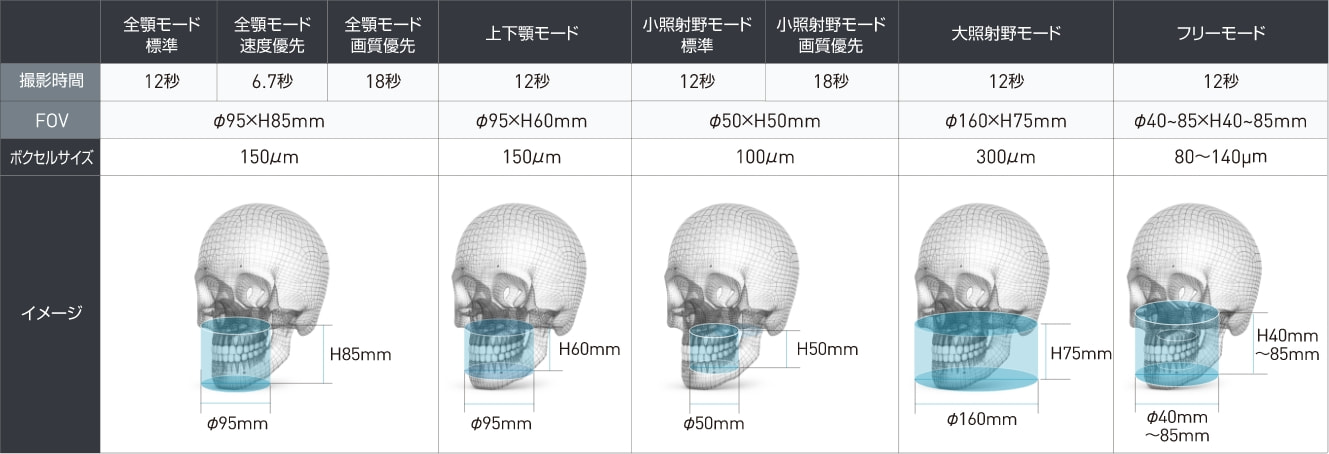

最短6.7秒、通常12秒で高画質CT撮影を実現

短時間での撮影は、被曝量を抑えることにつながり、患者さんの負担を軽減することができます。

BEL-Xでは、すべての撮影モードで12秒、さらに高速モードでは6.7秒の短時間撮影が行え、患者さんが動く事で起こるアーチファクトの軽減が期待できます。

多様なFOVサイズに対応

数歯に限定した小さなサイズから、全顎と顎関節を含む大きなサイズまで、用途に合わせた多様なFOVサイズの撮影を行うことができます。

撮影仕様:CT

| 項目 | 内容 |

|---|---|

| 撮影種別 | 全顎(標準)、全顎(速度優先)、全顎(画質優先)、上下顎、 小照射野(標準)、小照射野(画質優先)、大照射野、フリー |

| FOV | Φ40×H40㎜(フリー)~Φ95×H85㎜(全顎) Φ160×H75㎜(大照射野) |

| ボクセルサイズ | 80~300㎛ |

| 照射時間 | 12秒(標準)、6.7秒(速度優先)、18秒(画質優先) |